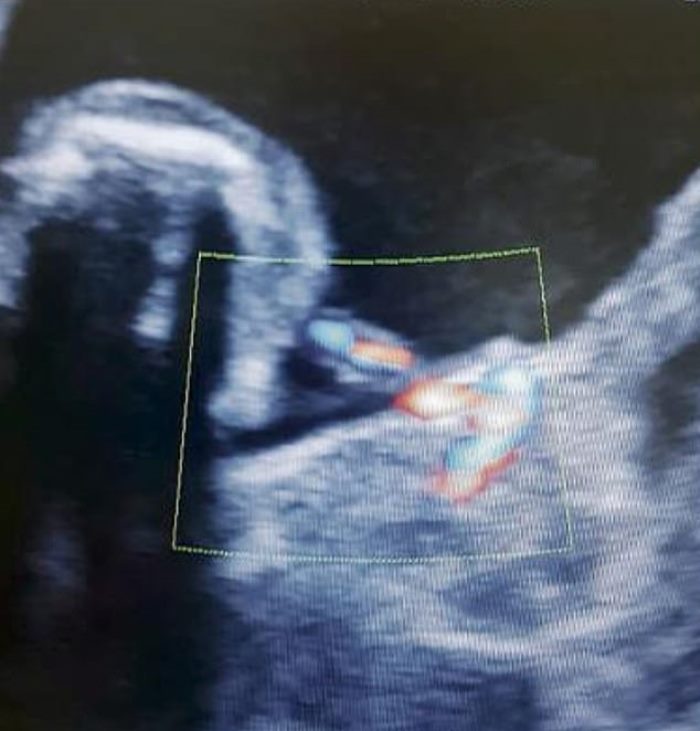

The girl’s mother, Monica Vega, said that doctors found something inside Itzamara’s abdomen when she was seven months pregnant.

It was the baby’s twin sister growing inside her small belly in its own amniotic sac, with legs, arms and umbilical cord, according to Los Informantes.